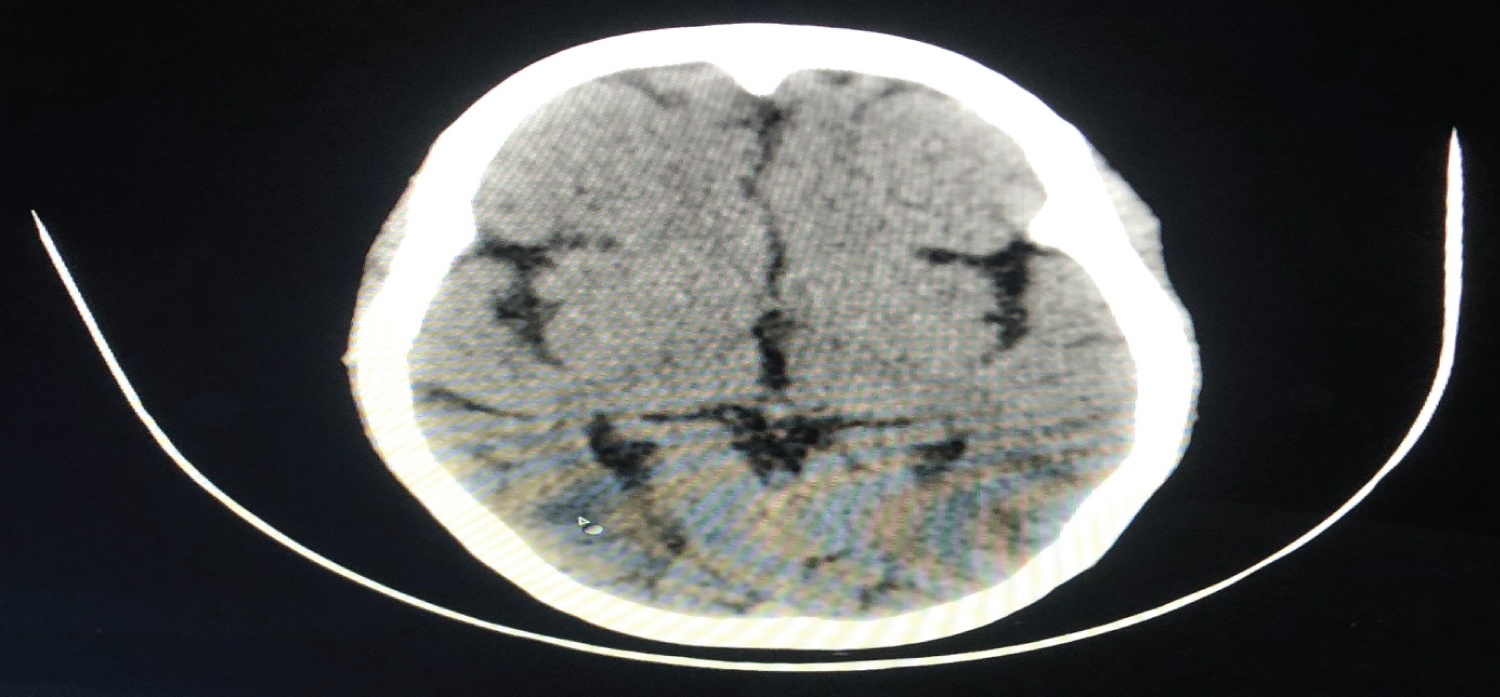

Another patient with a history of postpartum generalised tonic-clonic seizures was admitted to the emergency department. Patient was unconscious, with a pulse rate of 105 beats per minute, a blood pressure of 190/110 mmHg, and a GCS of 7/15. There was no prior history of pregnancy-related hypertension or epilepsy. The patient was managed with magnesium sulphate, levetiracetam, mannitol, furosemide, steroids and was started on nitroglycerin infusion for 24 hours while still on ventilator support. Thereafter, labetalol infusion was administered. The NCCT brain revealed bilateral parieto-occipital cortical and subcortical regions with symmetrical hypodense areas, which is suggestive of PRES. Patient spent 10 days in ICU without any incidence of seizures before being transferred to the ward (Figure 3).

Figure 3: NCCT head showing symmetrical hypodense areas involving cortical and subcortical region of bilateral parieto-occipital region. View Figure 3